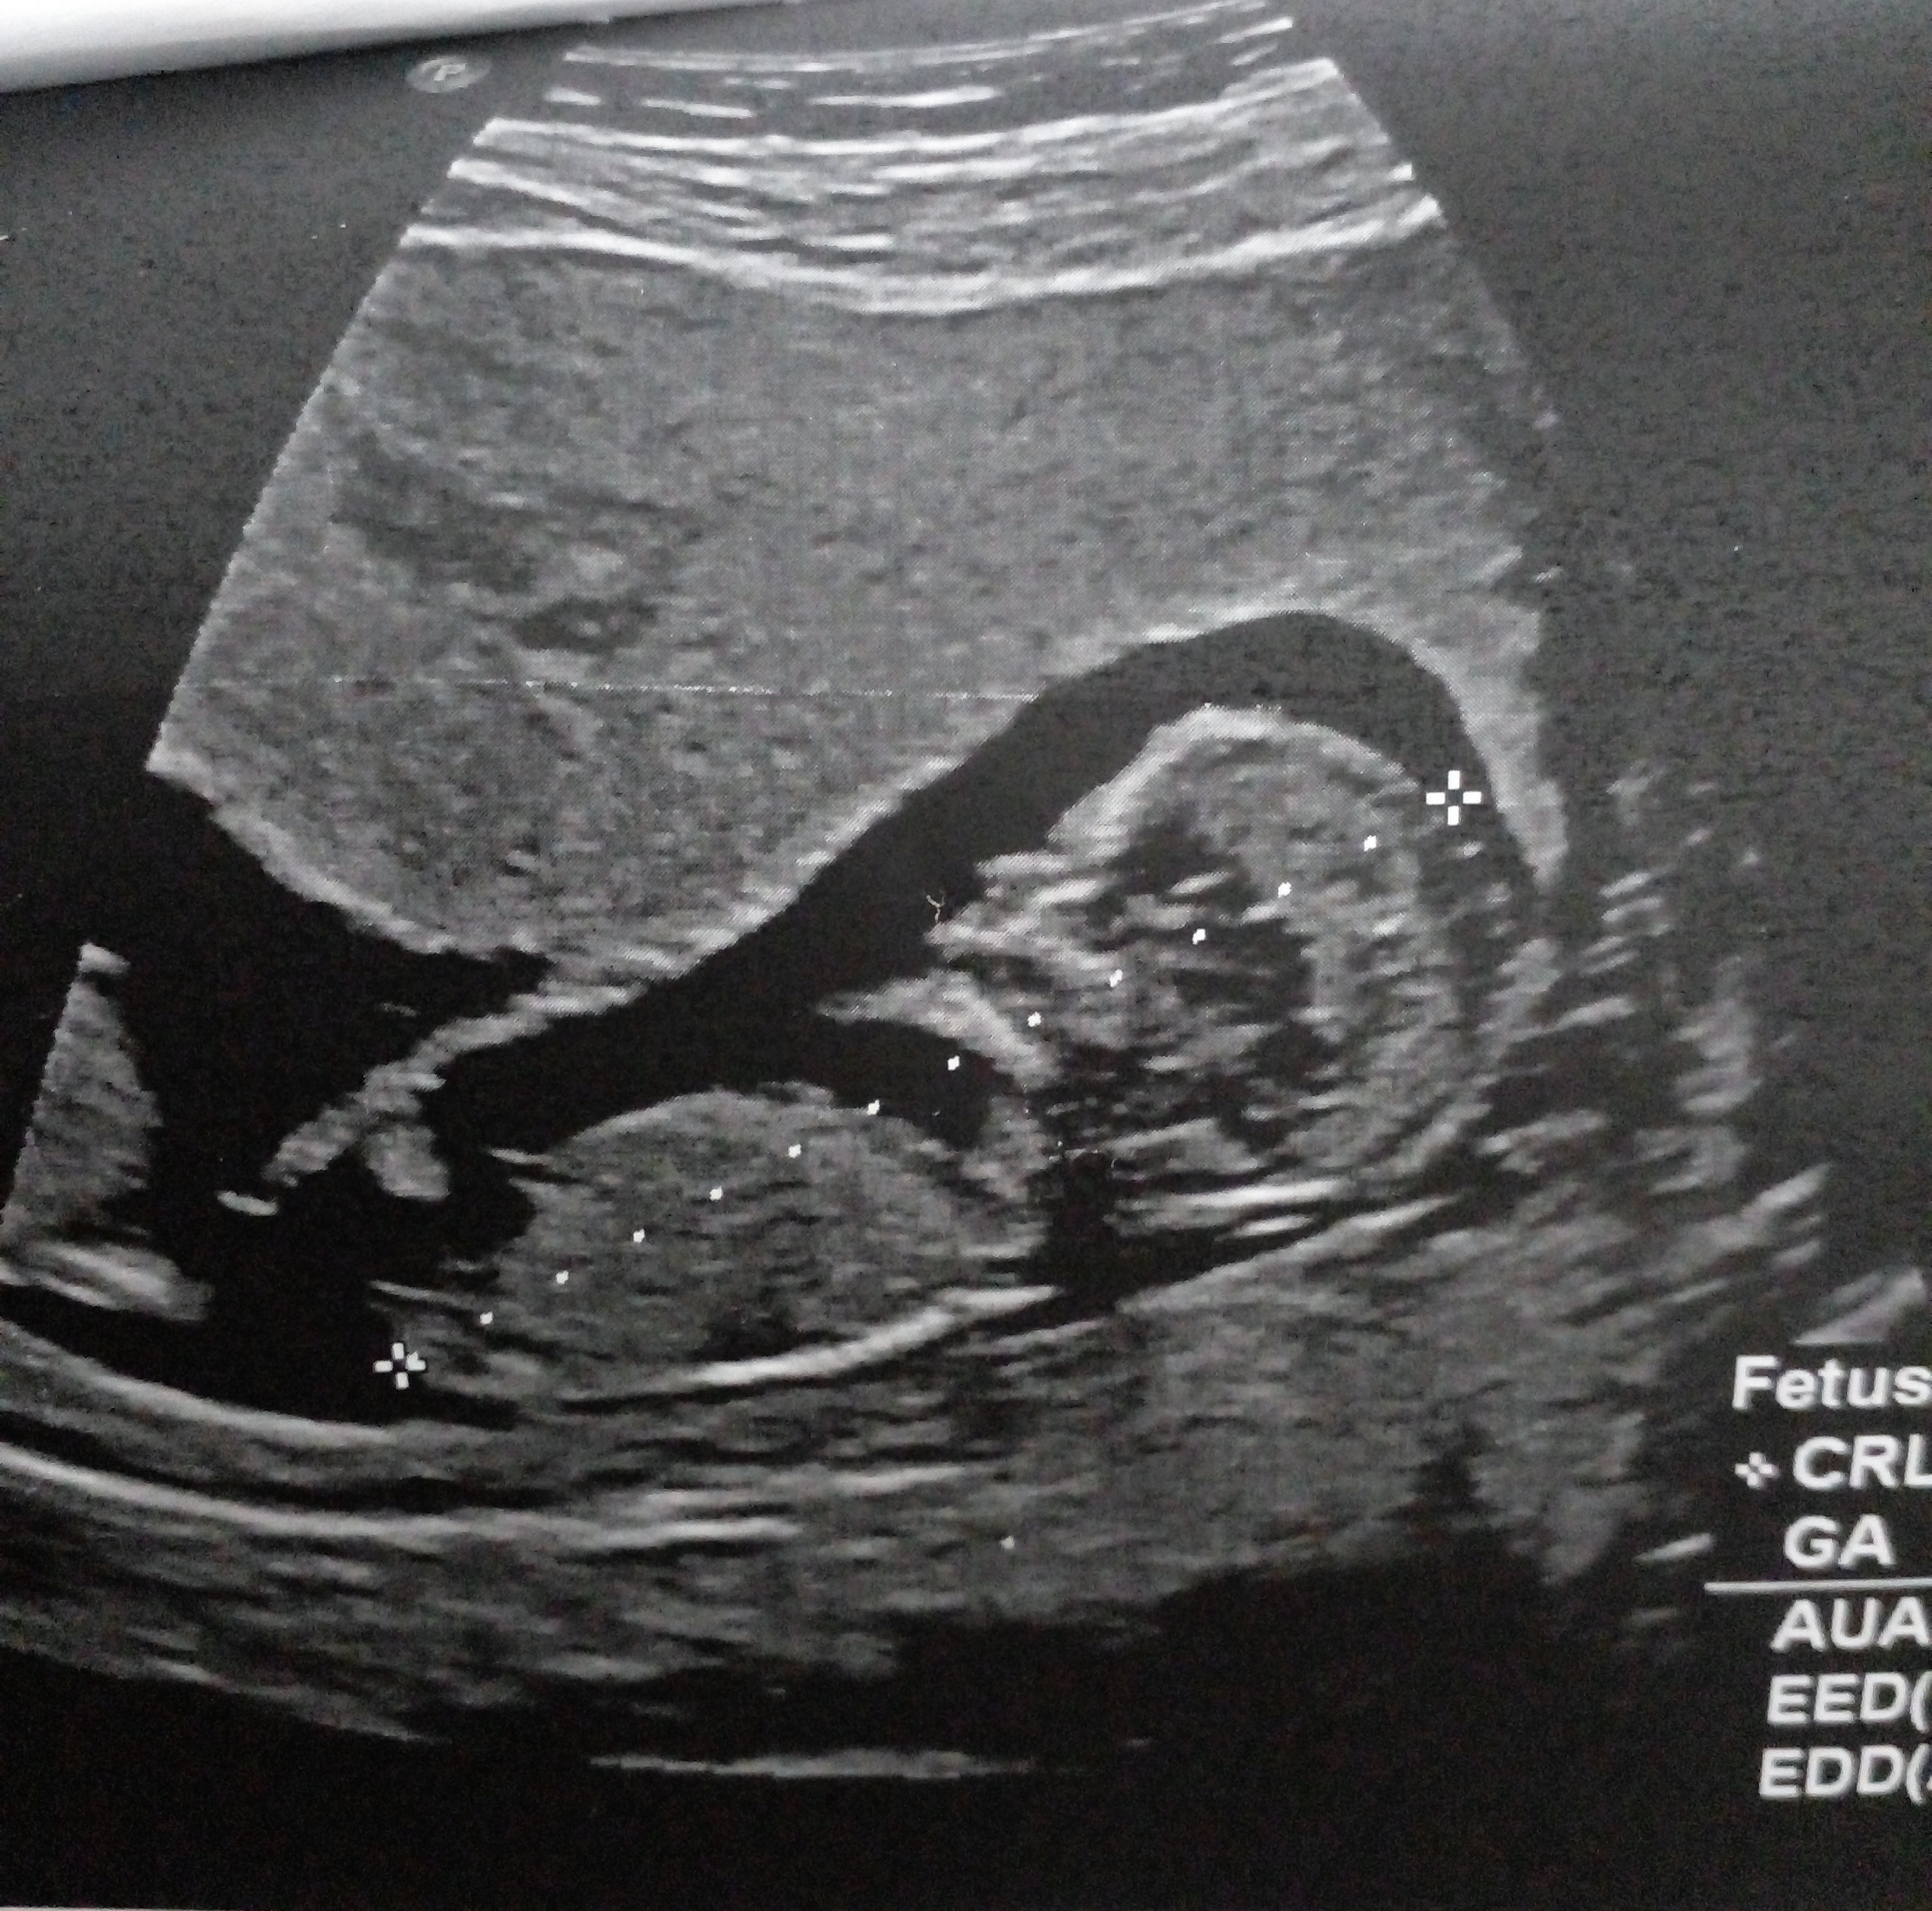

اخی عزیززززم بسلامتی. من میگم یه پسر یه دختر. اسی علایمت چی میخام بدونم دوقلو داشتی علایم بارداریت چیا بود قبل اینکه بری سونو بفهمی دوقلوه.

عزیزم انشاله خدا بهترین ها رو نصیبت کنه ، فقط بتای بالای داشتم بقیه علایم مشابه بقیه بود

ممنون عزیزم واقعا از روی عکس مشخصه یا حدس میزنید ؟ انشاله بهترین ها قسمت خودتون بشه

امیدوارم ب حق فاطمه زهرا ک سلامت و تندرست بیان بغلت خیلی حس خوبیه بمونن برات 😍❤️❤️❤️❤️

والا تا جایی ک تجربه دارم باید همین باشه ی گل پسر ی شاهزاده خانوم

حالا 18 هفته ک رفتی آنومالی تگم کن ببینم درست گفتم😄😄😄